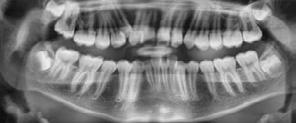

En la radiografía panorámica de inicio podemos ver la dentición mixta: con 38 dientes presentes, entre ellos los dientes temporales 63, 64, 65, 75, 84 y 85, los premolares y terceros molares y en formación (Figura 5).

En la radiografía panorámica, podemos observar 28 dientes presentes con los terceros molares en formacion así como el correcto paralelismo de todas las piezas dentales, (Figura 10).

Figura 5. Radiografía Panorámica. Figura 6. Intraoral de frente, derecha, izquierda. Figura 7. Arcadas superior e inferior.

Figura 8. Extraoral e intraoral de frente. Figura 9. Intraoral derecha e izquierda. Figura 10. Radiografía panorámica final. Figura 11. Comparación de inicio, progreso, final extraoral e intraoral.